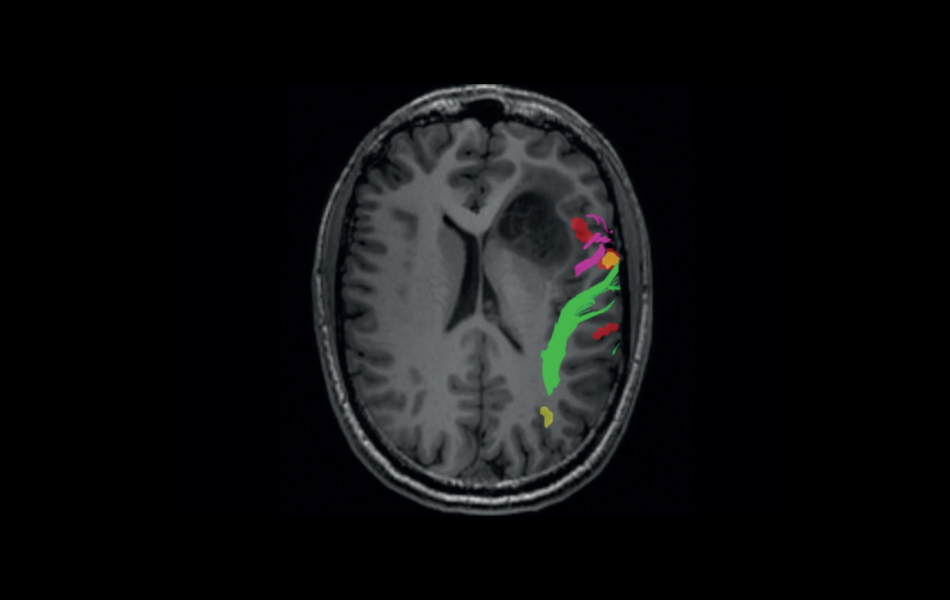

Functional MR (fMRI) (7.15.6)

The Functional MR application, powered by Olea Medical®, is integrated into Vitrea Advanced Visualization and is a seamless and intuitive brain mapping application to help assess critical areas and improve surgical planning.